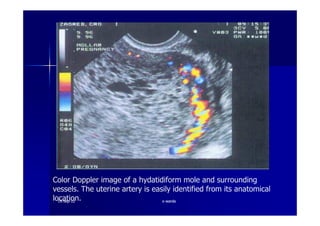

Color Dopplor facilitates visualization of the enlarged spiral

arteriesclose proximity to the “ snow storm” appearance

Color Doppler image of a hydatidiform mole and surrounding

vessels. The uterine artery is easily identified from its anatomical

location.1919--SepSep--1212 o wardao warda